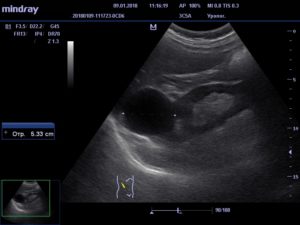

- Ультразвуковое исследование почек, позволяющее определить размеры, расположение и характер содержимого в капсуле новообразования;

- Магнитно – резонансная и компьютерная томографии, использующиеся для составления более полной картины и уточнения результатов, полученных благодаря УЗИ;

На основе результатов обследования и под контролем УЗИ в области локализации капсулы выполняется прокол кожи и мягких тканей. Специальной иглой уролог производит прокол капсульной стенки и извлекает из нее содержимое.